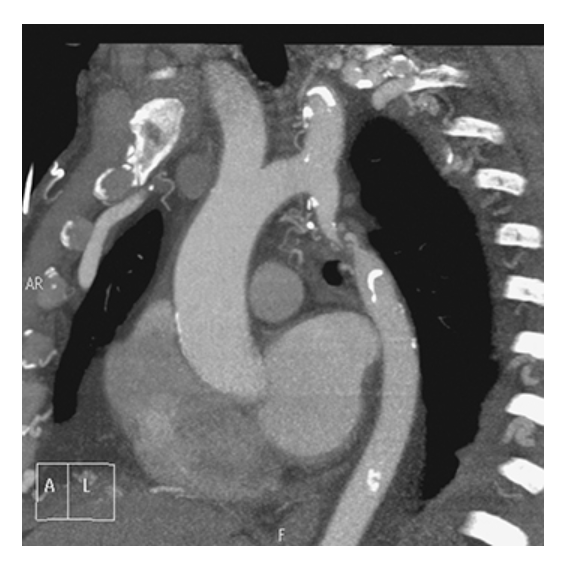

Aortic Regurgitation. Coronal oblique view shows moderate jet (dark, signal void) emanating from the aortic value into the left ventricle (arrow). There is also dilatation of the ascending aorta.